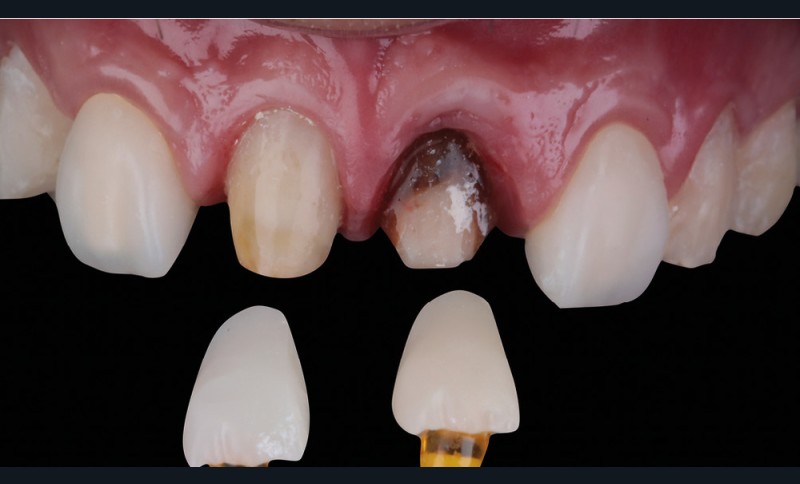

Acte 4 : préparation dentaire et gestion du rose additive (fig. 5 et 6)

À trois mois, les tissus en cours de cicatrisation se stabilisent ; nous passons à la préparation des dents [3].

Au vu des larges plages de cément exposées, nous optons pour une préparation de type couronne sur 53, 11, 21 et 23, afin de privilégier un assemblage prothétique de type scellement. Pour 15, 14, 24 et 25, nous resterons essentiellement dans l’émail et en vestibulaire. Ce choix nous oriente sur une préparation de type facette dont l’assemblage prothétique se fera par collage.

Nous observons que les tissus mous autour de la dent dyschromiée 21 se sont affinés et laissent transparaître le substrat radiculaire [4]. Un épaississement des tissus mous à l’aide d’une greffe de conjonctif s’impose. Dernières retouches également pour la ligne des collets par de petites gingivectomies au bistouri électrique. Des couronnes provisoires, basées sur le nouveau profil d’émergence, sont ensuite posées afin d’obtenir une cicatrisation guidée.